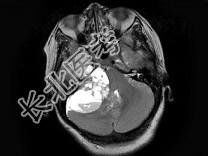

- 单项选择题女,37岁, 右耳听力下降半年,走路不稳2周, MRI检查如图,最可能的诊断为 ( )

A、听神经瘤

B、三叉神经瘤

C、胆脂瘤

D、小脑胶质瘤

E、未见异常